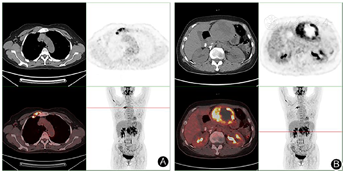

患者入院后查肝胆胰脾彩超提示:左肝混合回声团,肝癌待排。实验室检查提示:乳酸脱氢酶785 IU/L,乙肝核心抗体定量6.16S/CO,肿瘤指标无殊。查体:腹平软,剑突下轻微压痛、反跳痛。胸骨柄处肿胀明显,压痛阳性。MRI增强检查提示:肝左外叶占位,恶性肿瘤(肝细胞癌可能大)伴出血考虑(图1,图2)。为明确肿瘤转移情况,患者完善18F-FDG PET-CT检查提示:1.左肝外叶软组织肿块伴FDG代谢环形增高,首先考虑肝脏恶性病变;2.胸骨结核术后,胸骨柄右前方软组织结节伴钙化,首先考虑结核浸润(图3)。

以往文献关于使用18F-FDG PET/CT评估HEAML的报道有限。一些文献提出伴有肿瘤内出血的HEAML表现为FDG高摄取[10],坏死和FDG高摄取往往提示EAML的肿瘤生物学侵袭性[11]。本例PET-CT图像示病灶实质部分FDG代谢明显增高,内部坏死,可能提示其恶性潜能。FDG高摄取容易与其他FDG高摄取的肝恶性肿瘤相混淆,但在与HCC的鉴别诊断上有一定价值。低级别HCC由于葡萄糖转运蛋白-1表达水平较低,因此低级别HCC的FDG摄取较低。而高级别HCC具有更高的葡萄糖转运蛋白1表达和己糖激酶活性,FDG摄取有所增高,但总体仍低于其他肝原发恶性肿瘤[12]。

综上所述,HEAML与HCC的影像表现虽有交叉重叠之处,但"中心强化血管征"和强化模式的差别,以及在18F-FDG PET-CT上FDG摄取的不同,结合无肝炎、肝硬化病史,肿瘤指标阴性等临床资料,在影像上可以进行初步鉴别诊断,最终诊断仍有赖于病理。